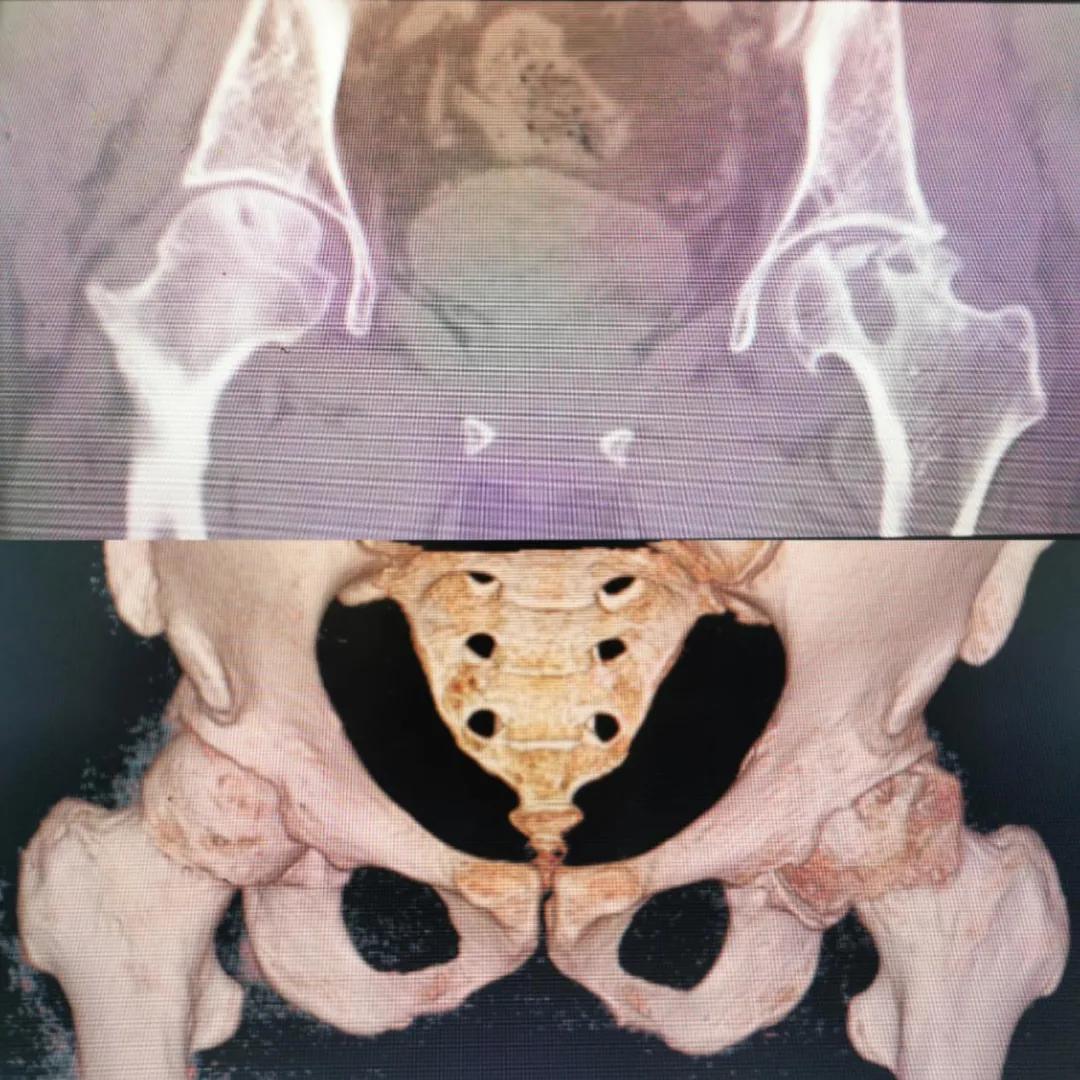

入院急查血結(jié)果提示炎癥反應(yīng),感染較重,凝血功能及肝功均不同程度損害;髖關(guān)節(jié)磁共振(MRI)檢查提示雙側(cè)股骨頭缺血壞死,繼發(fā)髖關(guān)節(jié)炎,左側(cè)髖周軟組織腫脹。醫(yī)療團(tuán)隊(duì)給出的初步診斷為膿毒血癥、股骨頭缺血性壞死、軟組織感染、皮膚潰瘍及閉孔神經(jīng)損傷。

圖片(圖為患者入院時(shí)髖部CT檢查)

追溯病史,患者訴前不久曾用蜂蜇療法治療股骨頭壞死,每日4次,每次100只蜜蜂蜇雙臀部、髖部,這才導(dǎo)致了病情急劇進(jìn)展。查明了來(lái)龍去脈,我院智能微創(chuàng)骨科醫(yī)護(hù)團(tuán)隊(duì)與患者家屬積極溝通病情,給予特殊級(jí)抗生素抗感染以及消腫、止痛等支持治療,同時(shí)對(duì)潰瘍創(chuàng)面進(jìn)行專業(yè)、規(guī)范的清創(chuàng)、換藥處理,保護(hù)創(chuàng)面降低感染程度;護(hù)理上輔助翻身,減少壓力性損傷。